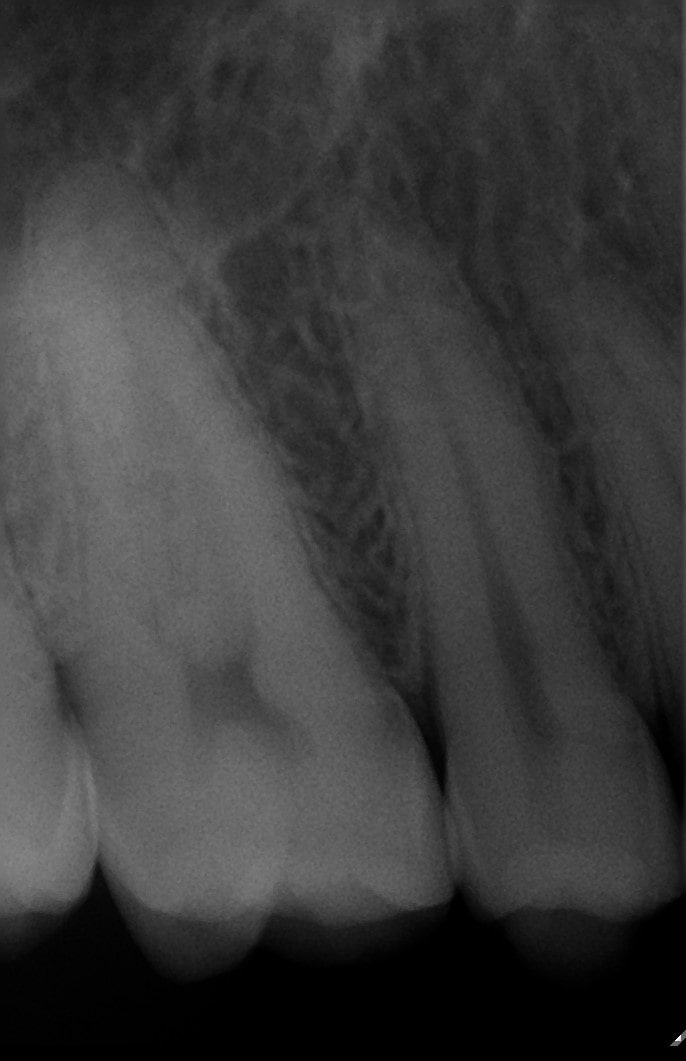

En radiologia, hay dos tipos principalmente, intraorales y extraorales.

Las intraorales son las radiografías de un conjunto de dientes o un diente en concreto, mientras que las extraorales son la Ortopantomografía muy utilizada para diferentes diagnósticos y la Teleradiografía Lateral de Cráneo para estudios de ortodoncia.